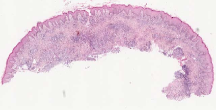

Curated dataset. Skin biopsies from 12 patients diagnosed with cutaneous leishmaniasis (spanning the disease differentiation spectrum) were acquired from Agha Khan University with Internal Review Board approval # 2024-9038-28175. Six of these biopsies, stained with hematoxylin & eosin (H&E), were scanned using Huron’s TissueScope digital scanner at 40X. A cheap-yet-clinical grade ($200) microscope (BS-2020MD Digital Microscope from BestScope International Limited, China) with a built-in digital 1.3 megapixel CMOS USB camera and 1W 5-LED illumination with Halogen Lamp 6V/20W was then used to capture videos for all 12 skin biopsies at 10X resolution. To show generalizability of our whole-slide image creation workflow for other common pathologies beyond cutaneous leishmaniasis, we also acquired videos for core biopsies of breast, liver, duodenum, stomach, and lymph node.

We demonstrate our WSI creation workflow on Leishmaniasis cases, as shown in Figures 1 and 4. An expert pathologist reviewed the cases and annotated granulomas as well as LD bodies on the stitched images and our generated images in Figure 4. To show generalizability of our approach, we also show results on core biopsies of breast, duodenum, stomach, liver, and lymph nodes (Figure 5).